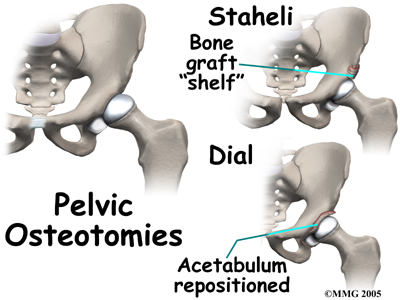

Surgical treatment for containment usually consists of procedures that realign the femur (thighbone), the acetabulum (hip socket), or both.

Realignment of the acetabulum is called a pelvic osteotomy. This procedure changes the angle of the acetabulum (socket) so that it better covers, or contains, the femoral head. To perform this procedure, an incision is made in the side of the buttock. The bone of the pelvis is cut and realigned in a new position. Large metal pins or screws are then inserted to hold the bones in the new position until the bone has healed. The pins usually must be removed once the bone has healed.

Osteotomy Types